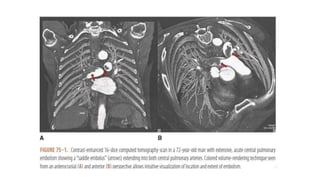

DIAGNOSTIC TESTS CT Angiography •Studies have shown sensitivity of close to 95% with an experienced observer • One of the most commonly cited benefits of CTA is its ability to detect alternative pulmonary abnormalities that may explain the patient's symptoms and sign • It allows adequate visualization of the pulmonary arteries down to at least the segmental level. • Contrast enhanced MDCT-PA is currently the preferred method of diagnosis.

• 39.

• RV toLV dimensional ratio of 0.9 or greater • IVS septal bowing towards LV • Reflux of contrast medium into inferior venacavae